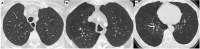

Fig. 10

Different types of emphysema: centrilobular, in which the central part of the acinus is predominantly affected (A); paraseptal, in which the distal part of the acinus is predominantly involved (B), and panlobular, in which the whole acinus is affected (C)